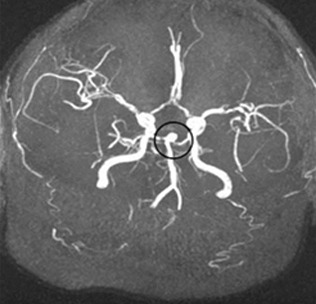

코일색전술은 뇌를 열지 않고 혈관 내에서 동맥류를 치료하는 방법으로, 대퇴동맥을 통해 삽입한 카테터를 이용하여 동맥류 내부에 백금 코일을 채워 혈류를 차단하는 시술입니다. 이를 통해 동맥류의 파열을 방지할 수 있습니다.

코일색전술은 모든 뇌동맥류에 적용할 수 있는 것은 아니며, 동맥류의 위치, 크기, 모양, 환자의 전반적인 건강 상태 등을 종합적으로 고려해야 합니다. 또한, 시술 후 정기적인 추적 검사가 필요합니다. 코일이 제대로 자리 잡고 있는지, 재발 가능성이 없는지를 확인하기 위해 CT 또는 MRI를 통한 검사가 주기적으로 시행됩니다.